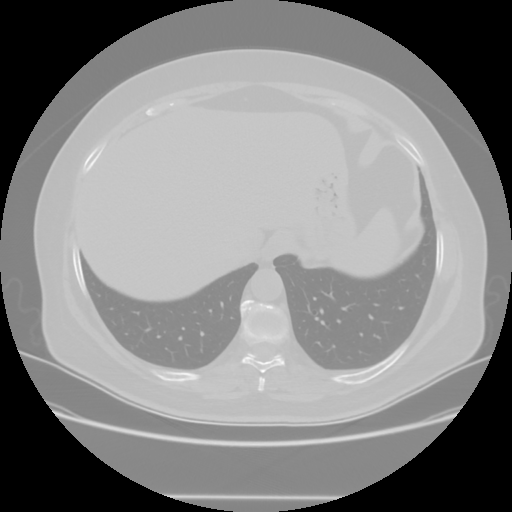

Original VENOUS CT scan

No window - Raw intensity values

Lung window (WL -600, WW 1500 β†’ Low βˆ’1350, High +150)

Mediastinum window (WL 40, WW 400 β†’ Low βˆ’160, High +240)